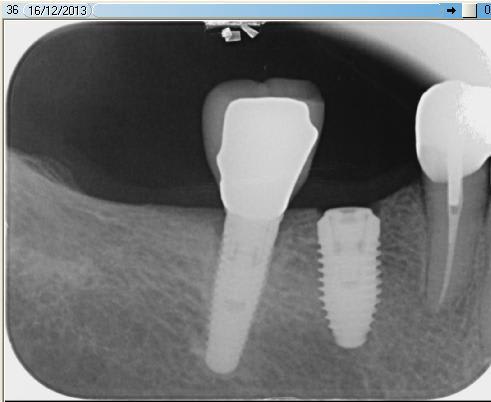

Voici la photo de l'implant...

Cica ou couverture ? A la radio c'est couverture, dommage c'est pas utile

Sur la radio je ne vois pas trop de pb d axe mais effectivement il est un peu trop distal.

Faudra peut être retoucher la face mesiale de la 7.

C' est un piege au niveau des 6 liée à la forme de la mandibule et la position de l opérateur de décaler la pose en distale. L os est souvent + large aussi dans cette zone et c' est bien tentant.

D après la radio il y avait un peu de marge....

D ailleurs Lounille a très bien joué , vaut mieux mettre un implant plus court mais correctement enfoui.